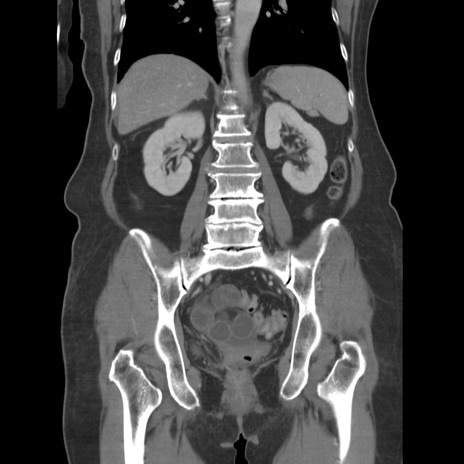

症例19(冠状断像)

【症例】80歳代女性

【主訴】下腹部痛

【現病歴】約8時間前より下腹部痛の出現あり、救急外来受診。

【既往歴】両側付属器切除

【身体所見】意識清明、下腹部正中に手術痕あり、その部位に一致して圧痛と反跳痛あり。腸蠕動音は亢進。

【データ】WBC 9300、CRP 0.15